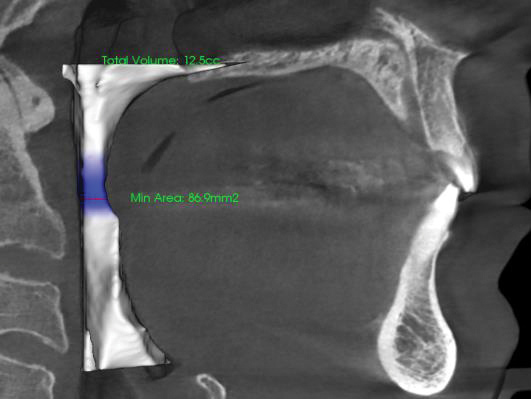

A comprehensive dental exam was performed that included a blood pressure test, an oral cancer screening, intraoral photographs, full mouth radiographs, a periodontal chart, a saliva test, and a CBCT scan. The exam confirmed the presence of active dental decay, periodontitis (ie, stage III, grade B), and areas of calcifications in his carotid artery (Figure 1 through Figure 3).

(2.) CBCT axial view of carotid calcifications.

Figure 2